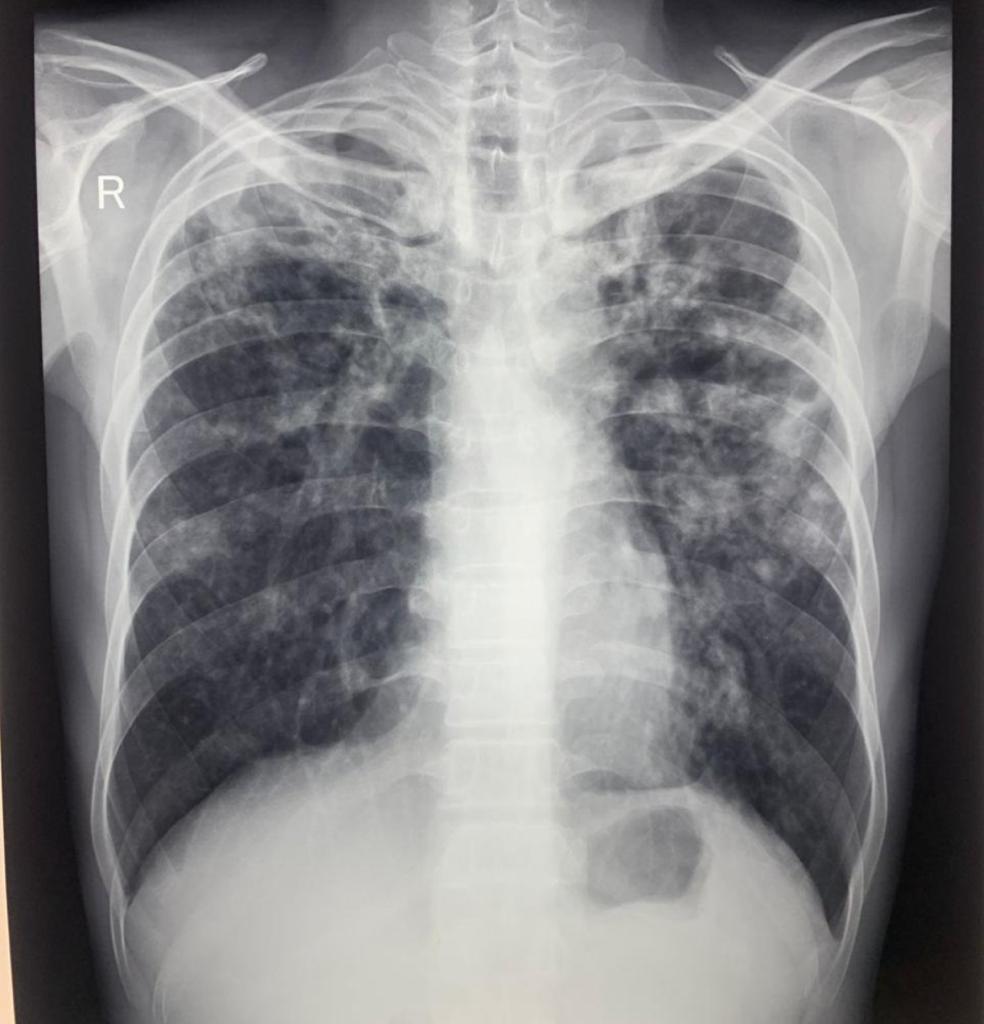

Tuberkulosis merupakan penyakit menular yang disebabkan oleh bakteri bernama Mycobacterium tuberculosis. Bakteri tersebut biasanya menyerang paru-paru, namun juga dapat menyerang bagian tubuh lain seperti ginjal, tulang belakang, dan otak.

Secara garis besar, kita membagi TB ini menjadi dua; TB Paru dan TB Ekstra Paru. Dari namanya, TB Paru sudah pasti dijumpai pada paru, sedang TB Ekstra Paru, adalah organ/lokasi dimana dapat dijumpai TB seperti pada selaput otak, kulit, kelenjar getah bening, usus, saluran kencing, tulang dan sendi.

- Batuk lebih dari 3 minggu

- Batuk kadang disertai dahak atau darah